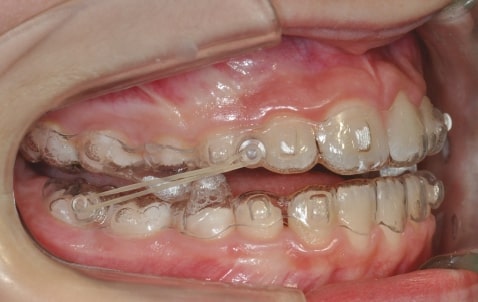

Treatment details

AngelAligner KiD 1 (aligners changed every 10 days)

• Upper frenulum surgery

• Class 1 both sides

• Overjet/Overbite Correction

Treatment setup

Treatment progress